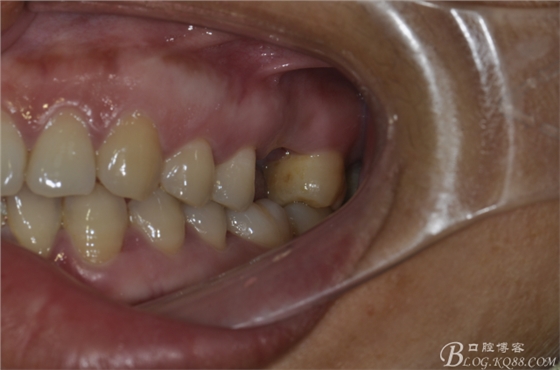

術(shù)前口內(nèi)照片。